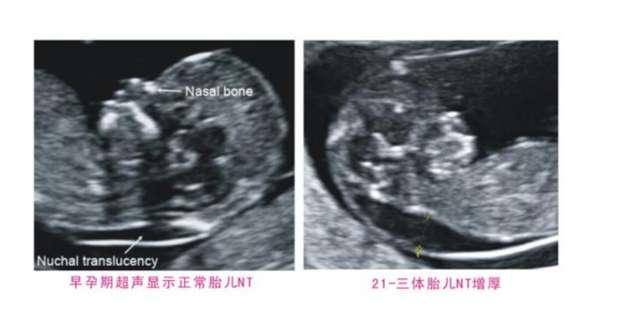

首先是胎儿NT检查了,主要检查胎儿颈项透明层厚度是否正常,在11-13周6天的时候是做NT的最佳周数,而且要求胎儿的头臀径在45-84mm之间。

NT一定要在最佳周数内进行检查,一旦提前或者延后,对于测量NT都是不准确的,NT主要检查胎儿颈部水平矢状切面与皮下组织之间的最大的厚度。

主要是为了排除胎儿染色体疾病的存在,预防唐氏儿出现的风险。

不过报告中最重要的一项内容,那就是胎儿的NT数值了,NT的正常范围是3mm以内,但一般超过2.5mm,就会提示NT高值,需要孕妈到上级医院进行相关染色体检查,来排除唐氏儿的风险。